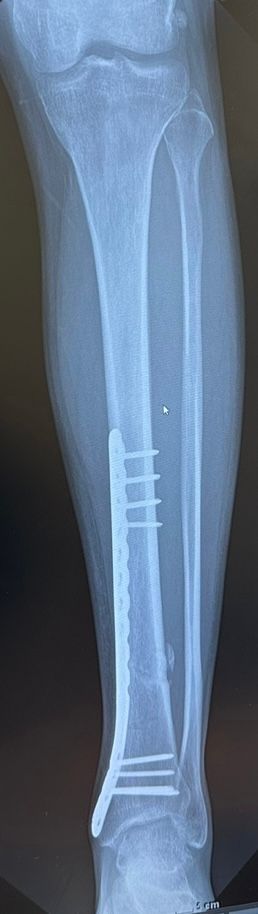

골절 후 엑스레이상 지금 상태가 어떤가요?

선생님 말로는 심하게 골절되어 시간은 좀 걸리지만 잘 붙고 있다고하는데 맞나요?

아래 엑스레이 상 뼈조각 같이 보이는건 뭔가요??

• 2번 째 사진

골유합은 잘 진행이 되고 있으신 것 같습니다.

뼈조각 처럼 보이는 것은 실제로 골절편이 전위되었을 가능성 및 골유합 과정에서 뼈찐 등이 퍼져나갔을 가능성도 있으나 치료과정에 큰 영향은 없으실 것 같습니다.